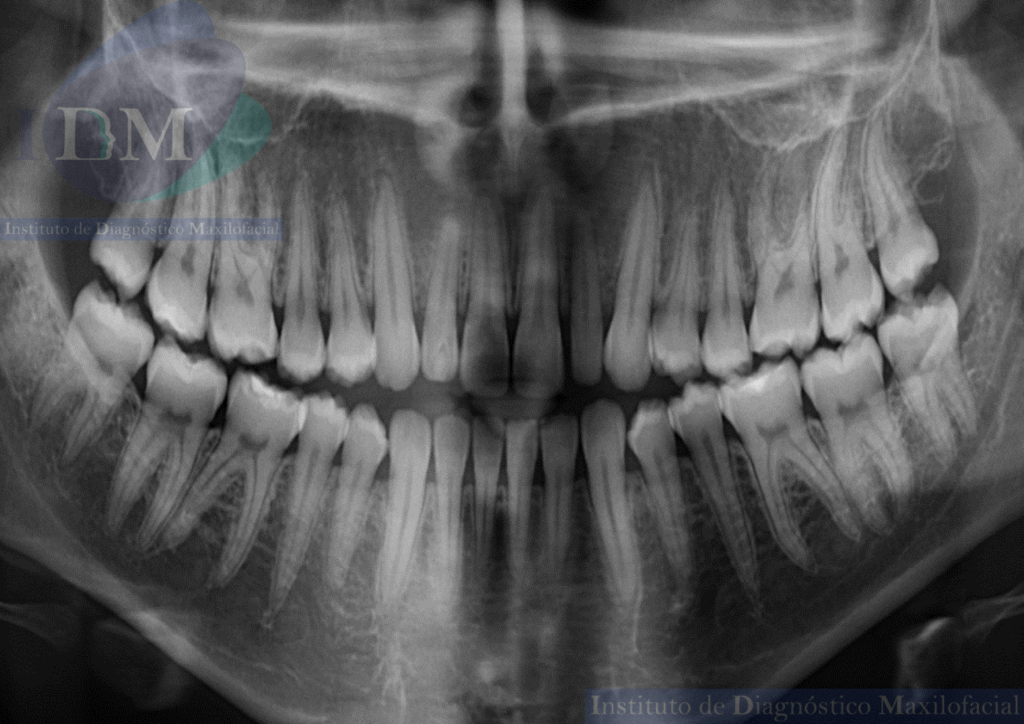

Radiografia Panorámica

A la evaluación de la radiografía panorámica se evidencia diastemas en sector dentario anterior con leve disminución generalizada de la longitud radicular.